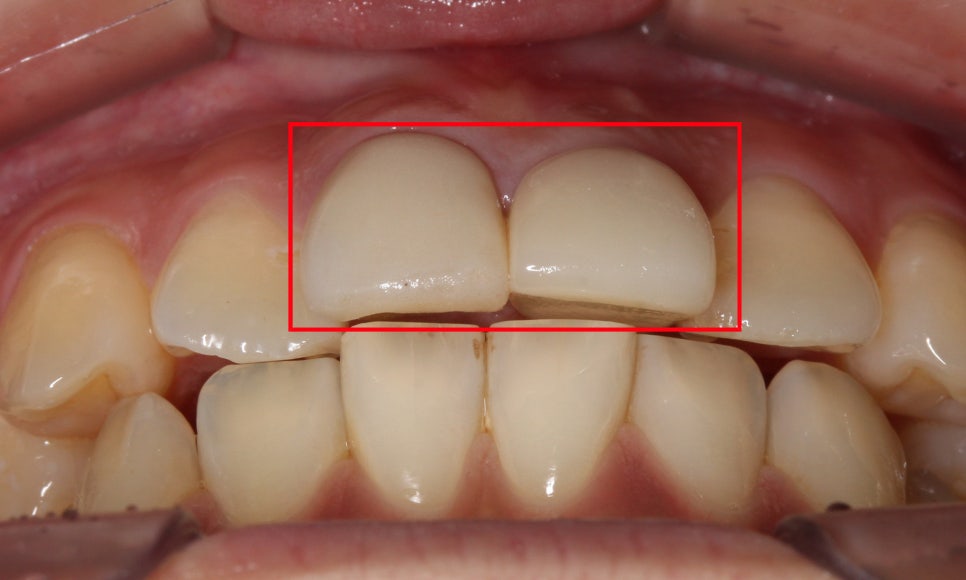

상악의 절단연을 보시면

중절치가 뻐드러지듯

돌출되어 있는 모습인데요,

측절치의 경우 중절치 옆으로

삐뚤게 맹출되어 있어

전치부의 심미성을 해치는 모습입니다.